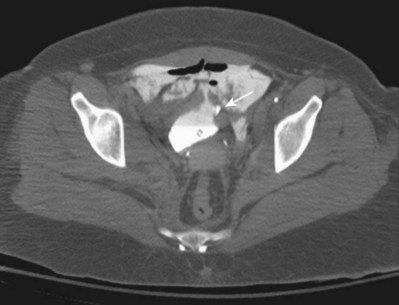

A dense, flame-shaped collection of contrast material in the pelvis is characteristic of extraperitoneal extravasation (Fig. 88–9). Depending on fascial integrity, contrast material may extend beyond the confines of the pelvis and be visualized in the retroperitoneum, scrotum, phallus, thigh, and/or abdominal wall. The amount of extravasation is not always proportional to the extent of bladder injury. Intraperitoneal extravasation is identified when contrast material outlines loops of bowel and/or the lower lateral portion of the peritoneal cavity.

Figure 88–9 Plain film cystogram reveals extraperitoneal bladder rupture with extravasation into scrotum. Surgical exploration revealed anterior bladder neck and prostatic urethral laceration.

Because CT is now routinely used to assess trauma patients, concomitant CT cystography is now frequently selected as a more efficient means to assess the bladder. CT cystography is as accurate and reliable as plain film cystography to evaluate suspected bladder injury (Fig. 88–10), as long as the bladder is filled in retrograde fashion with contrast material diluted to 2% to 4% (6 : 1 with saline) to a volume of 350 mL (Peng et al, 1999; Hsieh et al, 2002). Drainage films are not required after CT cystography because the retrovesical space can be well visualized with axial images (Morey and Carroll, 1997). Dilution of the contrast material is mandatory because undiluted contrast material is so dense that the CT quality is compromised by scatter artifact. Clamping the urethral catheter in an attempt to allow antegrade distention of the bladder by intravenous contrast medium is inadequate for diagnosis of bladder rupture—retrograde filling is required. Conventional abdominal CT of the trauma patient may show findings suggestive of bladder injury but is not considered to be adequate for bladder evaluation without retrograde contrast distention (Mee et al, 1987; Udekwu et al, 1996; Hsieh et al, 2002).